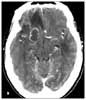

A CT scan of the head reveals several irregular lesions in both cerebral hemispheres and in the right cerebellar hemisphere, with surrounding edema (B).